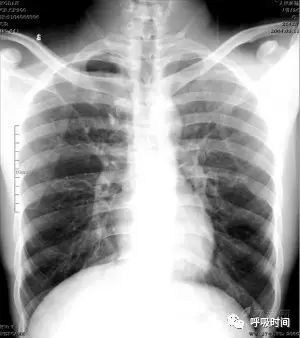

图 12 粟粒影——急性血行播散性肺结核并右侧胸腔少量积液。双肺弥漫分布的粟粒影,呈典型的三均:大小均匀、分布均匀、密度均匀。右侧肋膈角变钝(蓝箭头)